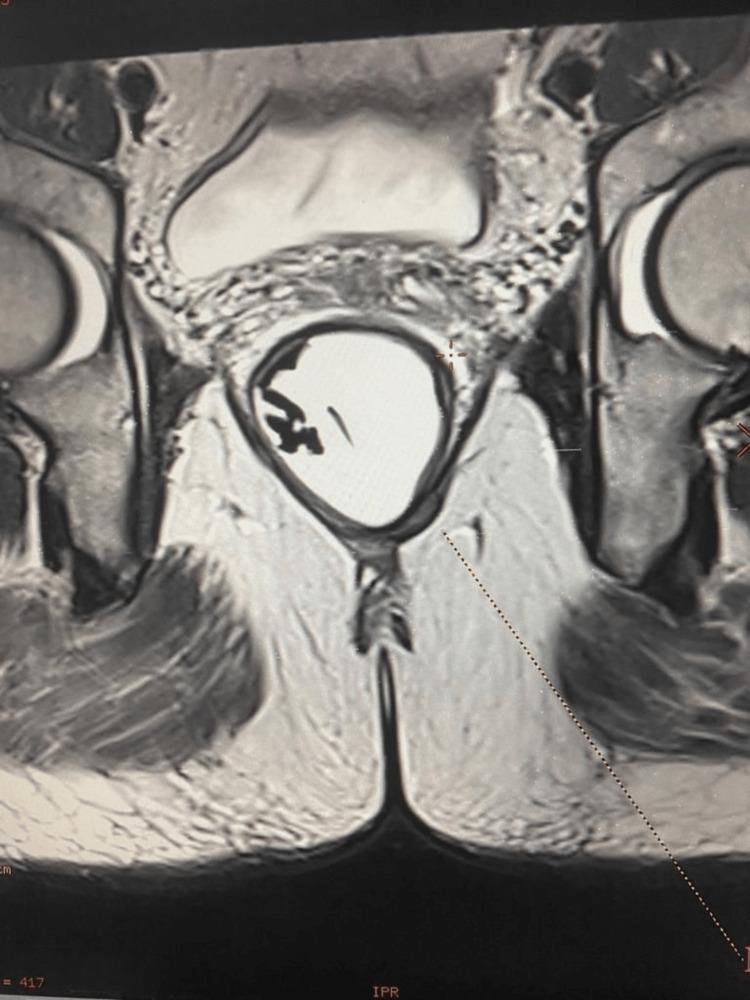

Gastrointestinal stromal tumors (GIST) are mesenchymal spindle cell tumors of the gastrointestinal tract with the rarest occurrence in anal canal sites accounting for approximately only 2-8% of the anorectal GISTs. GISTs involve the expression of KIT (CD117) tyrosine kinase with the presence of mutations in KIT or platelet-derived growth factor alpha (PDGFRα) and are identified as an important target in therapy. The elderly population in the age of 70s appears to be at the highest risk with abdominal pain, GI bleeding, anemia, or weight loss as non-specific presenting symptoms. Here, we describe a case of a 56-year-old man who presented with vague dull pain in his left buttock diagnosed with GIST with a submucosal mass in the posterior wall of the anal canal and rectum and a tumor size of 45x42x37 mm. An immunohistological study of the biopsy sample reported positive for CD 117, CD 34, and DOG 1. The patient was prescribed neoadjuvant imatinib for 8 months with a good response and subsequently underwent transanal endoscopic microsurgical resection. Post-operatively, the patient was continued on adjuvant imatinib followed by regular restaging CT chest/abdomen/pelvis and surveillance flexible sigmoidoscopy every 6 months.

胃肠道间质瘤(GIST)是胃肠道的间充质梭形细胞瘤,在肛管部位最为罕见,约占肛肠GIST的2-8%。GIST涉及KIT(CD117)酪氨酸激酶的表达,存在KIT或血小板衍生生长因子α(PDGFRα)突变,被确定为治疗的重要靶点。70多岁的老年人群似乎风险最高,腹痛、胃肠道出血、贫血或体重减轻是其非特异性表现症状。在此,我们描述一例56岁男性,其左臀部出现模糊钝痛,诊断为GIST,肛管和直肠后壁有一个黏膜下肿块,肿瘤大小为45x42x37mm。活检样本的免疫组织学研究报告显示CD 117、CD 34和DOG 1呈阳性。该患者接受了8个月的新辅助伊马替尼治疗,反应良好,随后接受了经肛门内镜显微手术切除。术后,患者继续接受辅助伊马替尼治疗,随后定期进行胸部/腹部/盆腔重新分期CT检查,并每6个月进行一次监测性乙状结肠镜检查。